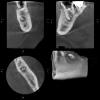

tomek Опубликовано 4 марта, 2013 Поделиться Опубликовано 4 марта, 2013 Осенью 2012 в районе нижнего первого моляра начались неприятные ощущения. Зуб как будто начал ныть - очень слабо, едва ощущалось. Этот зуб был запломбирован формалин резорцином очень давно, имеет темно красный цвет и никогда меня не беспокоил. В декабре 2012 решил все же сходить с стоматологу в городскую стомат. поликлинику. Сдалили снимок - обычный, прицельный маленький снимочек. Врач после осмотра и консультации с другими врачами, сообщил неприятную новость: на верхушке корня киста. Предложил два варианта: либо удалить зуб, либо пробовать закладывать лекарства в надежде что киста рассосется.Я выбрал второй вариант. Врач прочистил каналы, и прописал полоскать водой с солью и содой неделю. После он заложил лекарство (кальций) и направил прийти через месяц. Через месяц, сделали снимок и не обнаружили никаких изменений. Повторили процедуру с лекарством. Снова прошел месяц и все повторили, сделав снимок. Снова никаких изменений. Врач сообщила, что дальше лечить нет смысла, нужно удалять.Я отказался, мотивируя тем, что хочу сохранить зуб. Тогда мне были выданы все снимки на руки и посоветовали обратиться к другим специалистам (может чего посоветуют). В этот же день я обратился в дорогую приватную клинику. После осмотра снимков, врач сказал, что это прицельные снимки и по ним ничего не возможно увидеть. Сообщил, что нужно сделать 3д снимок на томографе. Я согласился, мы его сделали. Также мне выдали диск с программой , где я могу в 3д виде просматривать его в разных проекциях ( и сохранять на диск). Я прилагаю снимок, где киста видна наиболее отчетливо. Итак, врач сообщил по снимку следующее: предыдущий стоматолог даже не добрался до самой кисты, поэтому весь ввод лекарства был бесполезным - якобы стоматолог прошел лишь 1\3 длины корня. Но ведь я отлично помню, как предыдущий врач запихивал иголки (не знаю как правильно назвать) в сами каналы очень глубоко, упираясь в что-то твердое в самом зубе. Как такое может быть? По лечению, врач сказал, что здесь налицо склероз каналов и нужно приложить немалые усилия, чтобы добраться до кисты. После этого, будем закладывать лекарство в очаг воспаления. Но и есть вероятность, что нам это не удастся вообще добраться до кисты, и тогда показание к удалению зуба. Разумеется, я изучил все материалы в интернете на эту тему. Выяснил, что сегодня лечат лекарством, далее (если не помогает) делают резекцию верхушки корня. Также некоторые применяют метод депофореза - эффективность до конца неясна - некоторым помогает, некоторым нет.Самый эффективный способ, - метод лазера. Собственно, все это я выложил врачу. Он сказал, что депофорез применять смысла нет, так как каналы закрыты, и пока мы не доберемся до кисты, все это не имеет смысла. Тоже самое и с лазером - нужно сначала расчистить канал до самой кисты. Собственно, я бы уже и начал лечение, однако клиника очень дорогая. Собственно правда ли в словах нового стоматолога, что каналы также закрыты? То есть нерасчищены? Неужели это такая трудоемкая процедура? Ведь те клиники, которые применяет депофорез например, наверняка делают такую прочистку всегда и нигде я не встречал отзывов , что может быть такая проблема с тем, чтобы добраться до самой кисты . Вообще неясно, нужно ли это вообще. Если предположить, что предыдущий стоматолог все делала правильно , и вводя бур, доходила до верхушки корня, то может ли такое быть , что этого банально не видно на снимке? Не будет ли это новое лечение по сути таким же как старое (ввод лекарства) , просто в более широком просвете канала? Ссылка на комментарий